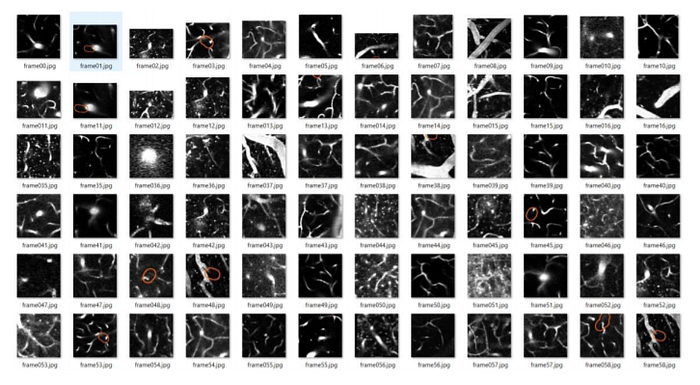

- After extracting the frames and manual filtering of the images, a dataset of 78675 images in total was created. If we observe the dataset in a scrupulous manner, we find out that the difference between the images as a whole is quite inconsequential. The difference between both the classes viz. blood flowing and stalled in the cranial vessel can be determined only by the region outlined in these images. So, unless and until we consider just the outlined region, the difference in both the classes seems irrelevant. Hence, extraction of the outlined region in a particular image becomes extremely important.

3. Furthermore, once the frames were extracted from the videos, these images were cropped to train the classifier. Regions of blood flow and stalled vessels were randomly cropped from the extracted frames.

4. This exercise was performed to train the classifier in a more efficient way by omitting the unnecessary parts and extracting the necessary data from the images.